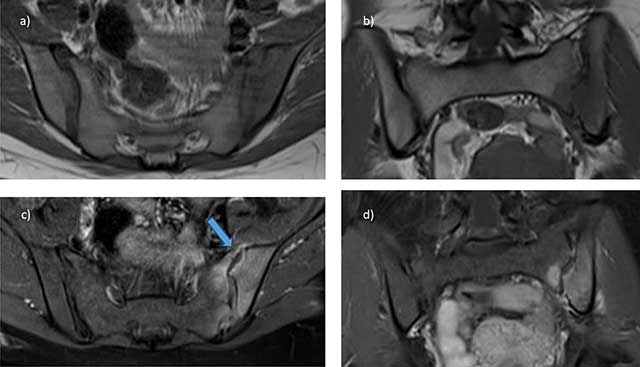

Figure 15

Pyogenic arthritis of the left sacroiliac joint in the postpartum: axial a) and coronal b) T1 MR images, as well as axial c) and coronal d) Fat-suppressed T1 MRI images after gadolinium administration show fluid collection in the joint space (arrow), associated with bone and soft tissue edema.